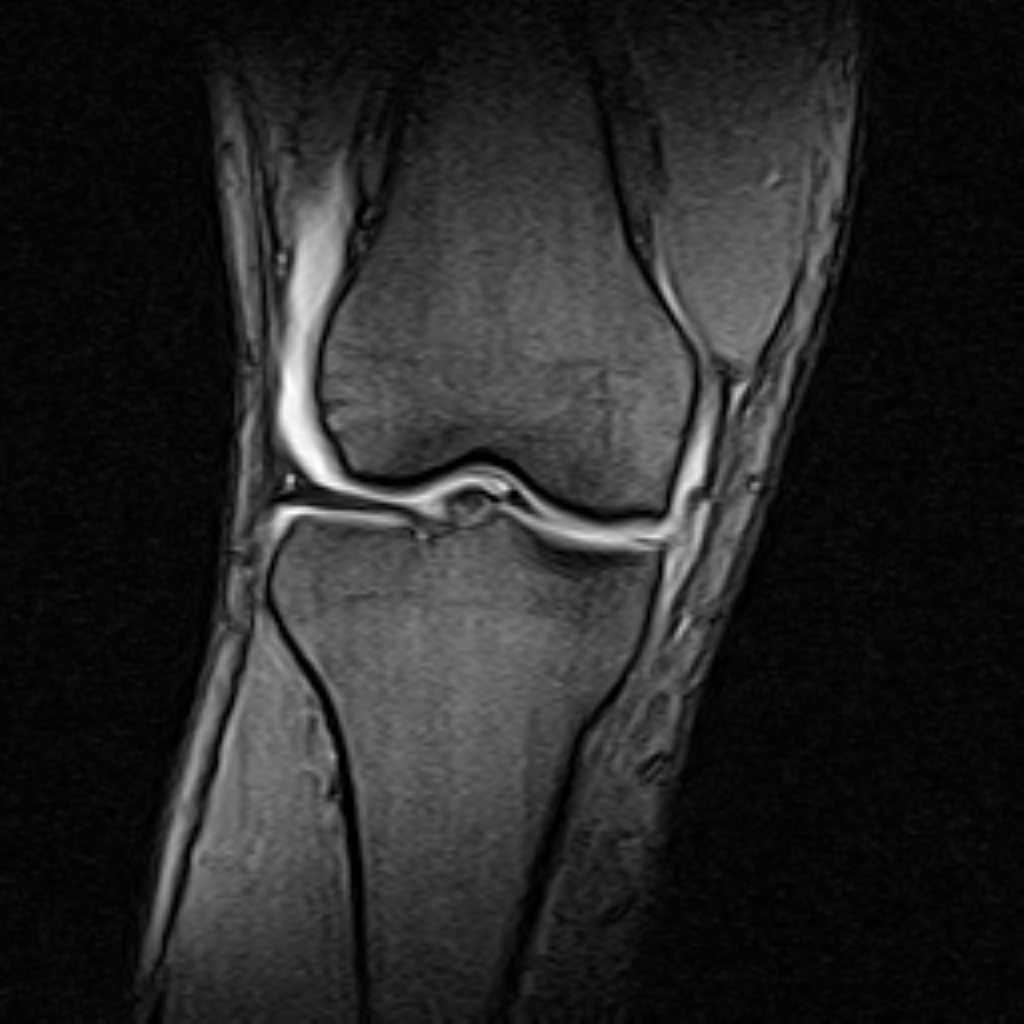

RIGHT KNEE MRI

(Without contrast)

The bones comprising the knee joint are normal in signal and configuration.

The cortical bone has normal thickness.

Bone marrow signal is normal .

The hyaline cartilage covering patella, fermoral condyles and tibial plateau shows normal signal and thicknees.

Lateral meniscus displays normal configuration .

PCL ,MCL & LCL are intacted.

Patellar ligamentum and quadriceps tendon are normal in shape and signal intensity .

– Knee joint effusion with soft tissue swelling around the knee

– Longitudinal tearing of P.H. of medial meniscus with large bucket handle

– Complete tearing of ACL ( femoral detachment )